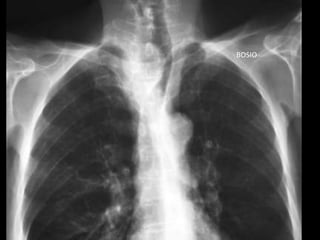

RADIOGRAFIA

• Radiografía normal

• Radiografía patológica

– Ensanchamiento mediastinal

• Técnica radiográfica

• Estructuras normales de tamaño o distribución atípica

• Estructuras vasculares

• Tumores

RADIOGRAFIA • Radiografía normal •Radiografía patológica – Ensanchamiento mediastinal • Técnica radiográfica • Estructuras normales de tamaño o distribución atípica • Estructuras vasculares • Tumores